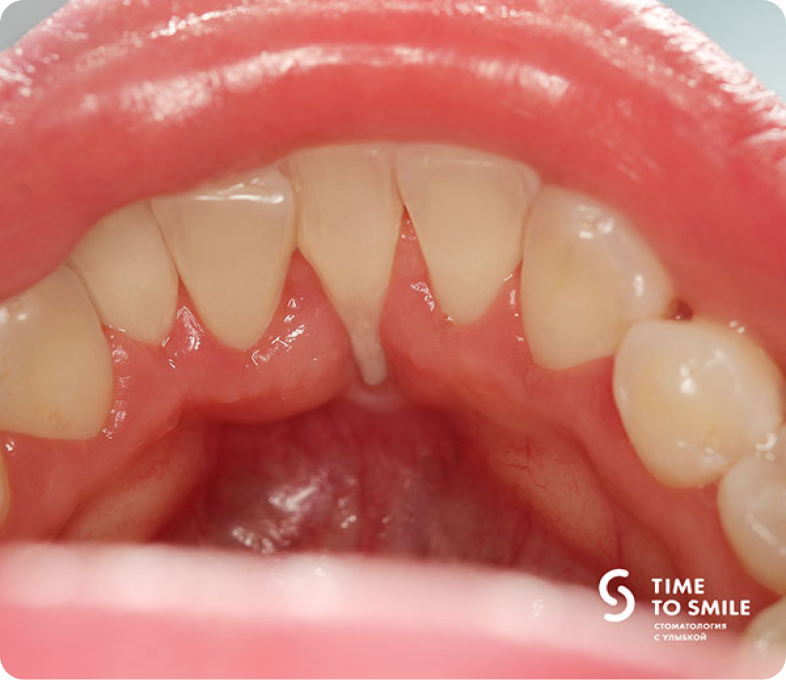

Через 3 месяца после операции наблюдаем практически полное закрытие корня нижнего резца и восстановление десны.